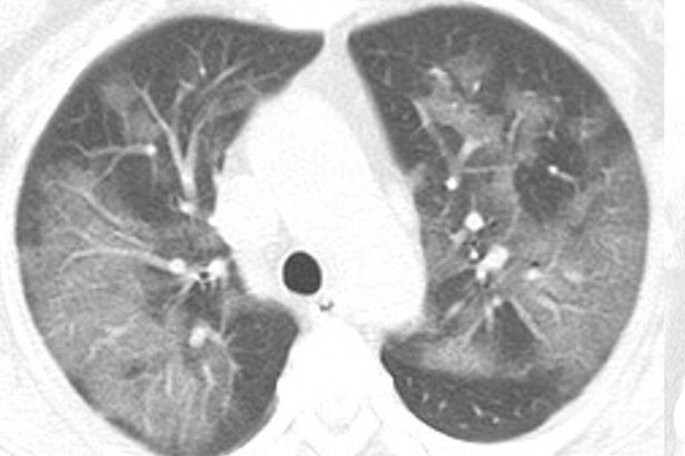

Κορωνοϊός: Ανατριχιαστική ακτινογραφία ασθενούς